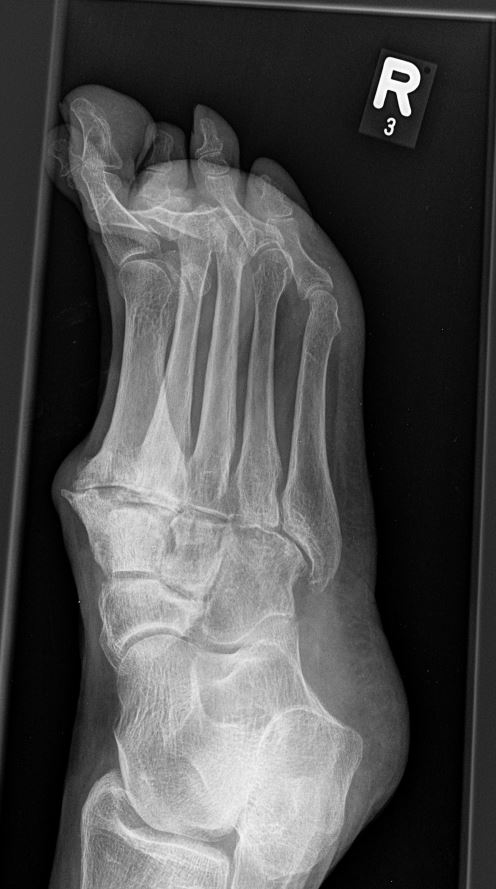

Häufig werden die Arthrosen der Lisfranc-Gelenklinie relativ spät diagnostiziert. Die Gründe dafür liegen oft daran, dass die Patienten selbst einen Schmerz an der Fußwurzel nicht mit dem Symptomkomplex Spreizfuß und Hallux valgus in Verbindung bringen. Auch werden in der Primärdiagnostik häufig nur vom Vorfuß Röntgenbilder angefertigt oder die angewandte Röntgentechnik erlaubt keine Einsicht in die Lisfranc-Gelenklinie.

Eine Röntgenaufnahme unter Belastung mit Abbildungen des ganzen Fußes a. p. (mit 15-20° Röhrenkippung) und seitlich, sowie Schrägaufnahmen, reichen meist zur Diagnose. Manchmal ist ein MRT und DVT ergänzend hilfreich. Selten wird die Indikation für ein SPECT CT gestellt (Abb. 6).

• konventionelle Röntgenbilder mit Belastung im Stehen a. p. und seitlich, ggf. schräg (Abb. 9, 10 und 11).